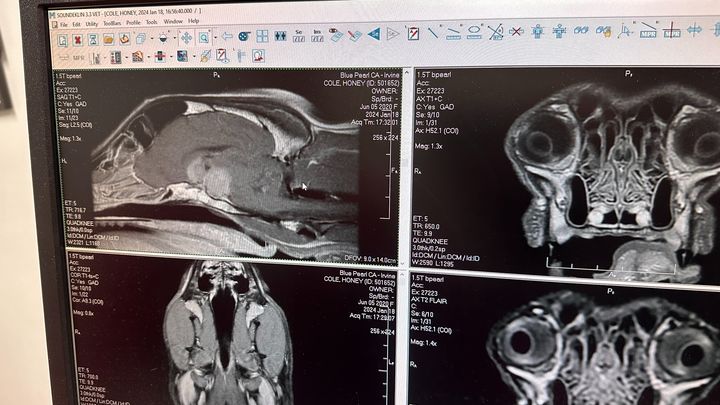

Hello my name is Kaylan Cole and after much contemplation, we've decided to reach out through this GoFundMe in the hope of receiving assistance as we face the overwhelming challenge of our beloved Honey's recent diagnosis. On January 18th, our three-year-old Border Collie Mix, Honey, was diagnosed with an incredibly rare pituitary macroadenoma tumor, leaving us with no option for a cure other than radiation.

This devastating news came upon us swiftly, and Honey, who is not just a pet but a cherished member of our family, has become the center of our concern. Desperate to ensure she has the chance for more healthy years, we're exploring every avenue possible, starting with radiation. The uniqueness of her case has left doctors astonished – they've never encountered a tumor of this size in a dog so young.

Attached are some photos of her as well as her MRI scan with the tumor.